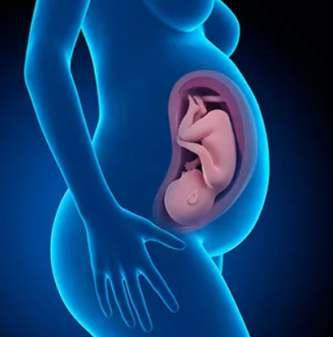

Para un buen le control prenatal recomendamos iniciarlo apenas sepa o piense que esta embarazada, incluso si solo presenta un fallo menstrual, para corroborarlaexistenciaonodeembarazo

En caso de embarazo deberá acudir cada mes a control o por lo menos por un mínimo de cinco consultas durante toda la gestación.

N o r m a l m e n t e d e b e n e f e c t u a r s e ultrasonidos en tres ocasiones al igual que las pruebas de laboratorio, uno por trimestre, esto puede variar si el embarazo es de alto riesgo como en las hipertensas, diabéticas,embarazosmúltiples,etc.

El ultrasonido ginecológico precoz, nos permite saber si estas embarazada hasta laquintasemana.

La ecografía genética o del primer trimestre tiene como pronóstico detectar alteraciones fetales como la presencia de anomalías cromosómicas, físicas y algunossíndromesgenéticos.

La Sonografía morfológica fetal, estructural o del segundo trimestre,

permite valorar la anatomía del bebé, d i a g n o s t i c a n d o a n o m a l í a s o malformacioneseneldesarrollo.

El ultrasonido del tercer trimestre, llamado perfil biofísico, es para analizar los movimientos fetales, la respiración, la actividad cardíaca, el tono muscular, la cantidad del líquido amniótico y el grado demadurezdelaplacenta.

Es importante que en cada cita se efectúe el examen físico completo enfatizando la tomadepresiónarterialyelpeso,quedebe aumentar de 8 a 10 kilos dependiendo con cuantolamujerinicieelembarazo.

Sedebeingerirácidofólicoidealmentetres meses antes del embarazo y continuarlo hasta el final. Aunque es recomendable continuar con las vitaminas durante el períodomínimodelactancia.